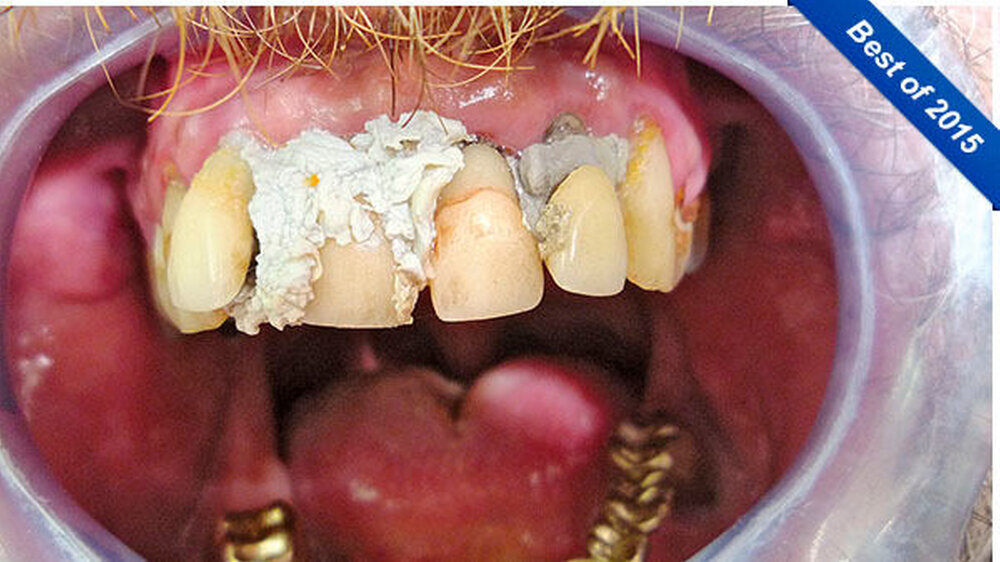

Seine Idee stattdessen: die Zähne selbst zu befestigen. Da er als Handwerker ist er im Umgang mit Baumaterialien versiert ist, sah er sich dieser Herausforderung gewachsen. Er kaufte sich im Baumarkt Fugendichtsilikon und umspritzte damit seine Zähne zur Befestigung. Farblich wählte er "manhattan-grau" und "steingrau" - diese Töne waren billiger als weißes Silikon.

Er achtete auch auf das Biokennzeichen, wie er betonte. Ein halbes Jahr lang war der Patient mit dieser Konstruktion zufrieden. Aber zur Weihnachtszeit gefiel ihm die graue Farbe seiner Silikonbefestigung doch nicht mehr, vielleicht, weil man ihn auch schon auf seine schlechten Zähne angesprochen hatte.